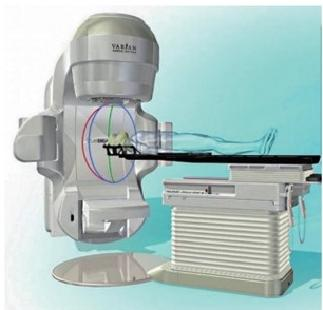

HyperArc technology

HyperArc is a non-coplanar stereotactic radiosurgery technology developed specifically for intracranial tumors. It has the characteristics of high precision, high efficiency and high automation. It has sub-millimeter accuracy and can complete the fixed-point radiosurgery treatment of several to dozens of brain metastases at the same time within 10 minutes, bringing better experience to patients with multiple brain me-tastases.

Our first case of HyperArc: October 28, 2020